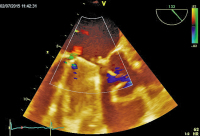

Mitralklappenprothese

Abbildung 1: Mehrere teilweise flottierende Vegetationen an der atrialen Seite der Mitralklappenprothese.